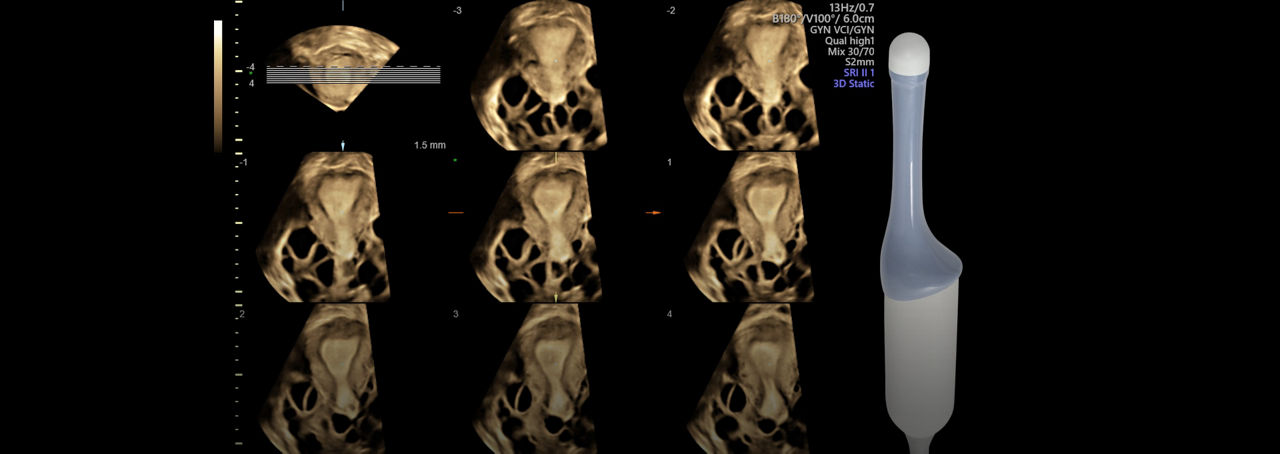

Practical, Easy 3D

With 3D features like SonoRenderlive, easily acquire fetal faces and use OmniView to obtain views not accessible with 2D. For another anatomical perspective add HDlive™.

SonoAVC™follicle

SonoAVC™follicle automatically calculates the number, dimensions, and volume of hypoechoic structures in a volume sweep to help monitor patient follicles faster.